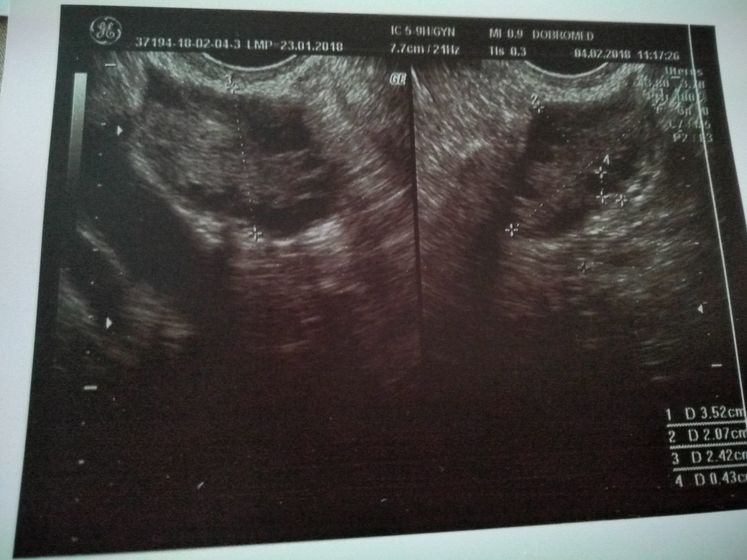

Поехали сегодня в пургу и вьюгу на УЗИ в Добромед(не в восторге) Сделали узи, рассказала что и как врачу, при осмотре было желтое тело, но как я поняла, не совсем то что нужно. В остальном все хорошо, матка, яичники все в норме. Критичного ни чего нет. Послали на ХГЧ завтра за результатом. Если есть, кто разбирается в заключении и в узи, буду рада информации. Тест все еще показывает //